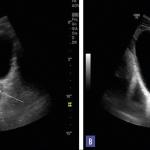

Tachycardie atriale focale

Un homme de 26 ans, militaire, consulte dans le cadre de sa visite de contrôle périodique d’aptitude au parachutisme...